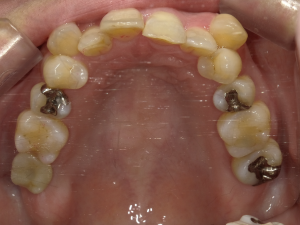

50代 女性 インプラント治療(GBR・ソケットリフト)

| 年代・性別 | 50代・女性 |

| 主訴 | Brの歯が取れそうなため、インプラントに変えたい。 |

| 部位 | 左下567 左上④5⑥ 右上67 |

| 治療期間 | 約3年9ヶ月 |

| 費用 | ¥3,224,500(税込) |

| 副作用・リスク |

|